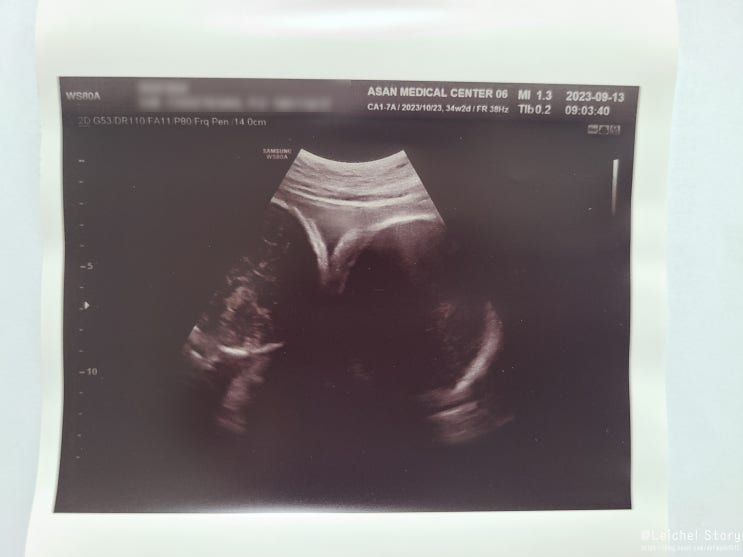

34주_쌍둥이 제왕입원 전 검사

3주 만에 아산병원을 다녀왔습니다. 3주 전만 해도 애들이 얼마나 클지 모르니 3주 뒤에 "태아 성장 ...